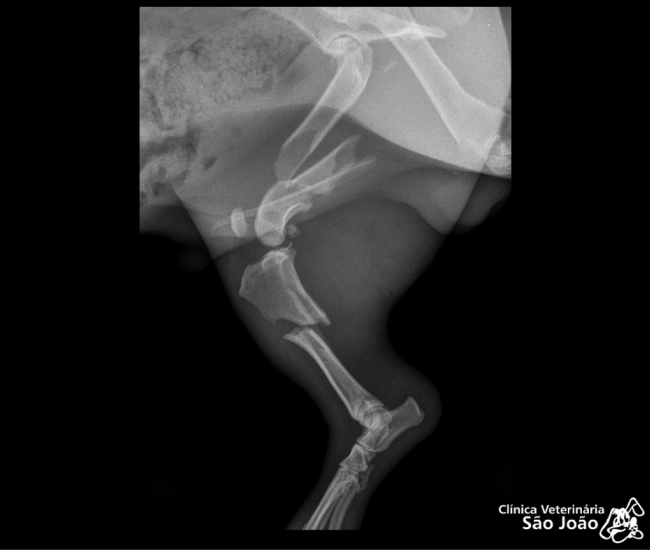

- Diferentemente do raio-x analógico, este raio-x oferece altíssima definição e todas as vantagens da tecnologia digital. É possível aproximar a imagem, trabalhar o contraste, exposição.O software permite ainda avaliações da medida cardíaca do animal e graus de displasia coxofemoral, por exemplo – explica o Dr. Nardeli Lucena.

O raio-x digital possibilita ainda a redução da radiação a que o animal deve ser exposto e também diminuição no tempo de duração do exame. O que se torna muito vantajoso tanto para o animal, quanto para o médico radiologista e para o acompanhante do animal ( que geralmente precisa permanecer na sala).